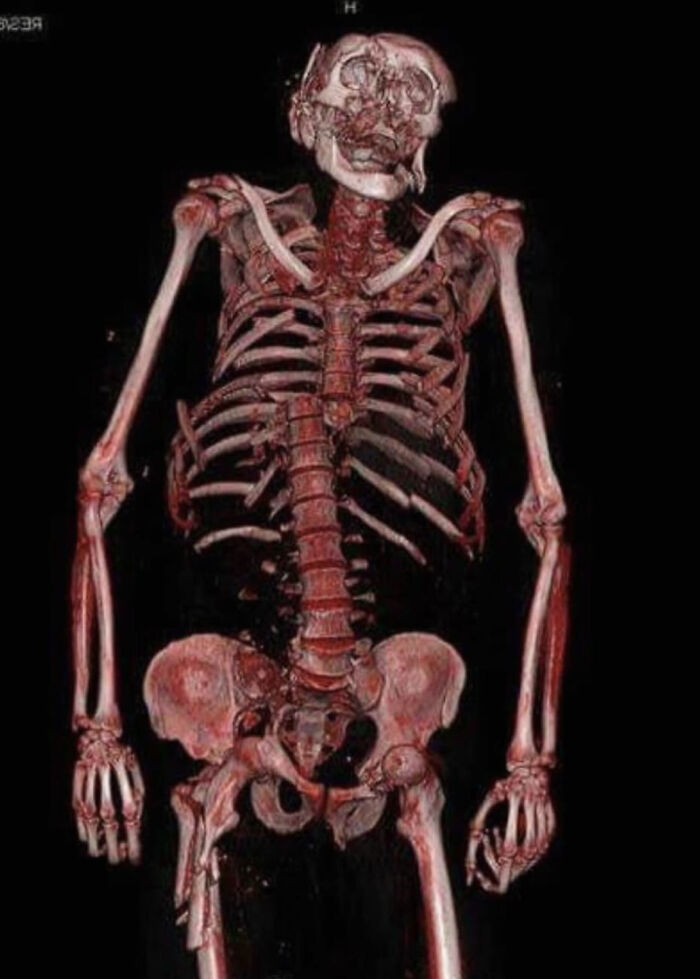

#14 This 3D CT Scan Shows Multiple Fractures As The Result Of A Motorcycle Accident At High Speed

Image credits: Emergentelman